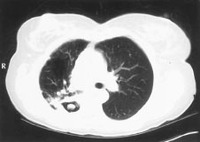

Signo de "halo" en la aspergilosis pulmonar temprana

De la colección del Dr. P. Chandrasekar; utilizada con autorización